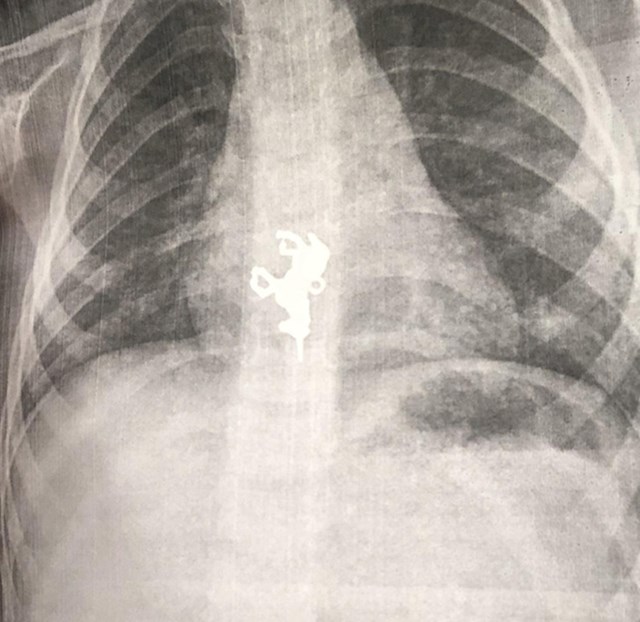

6. Jedan izlet u bolnicu